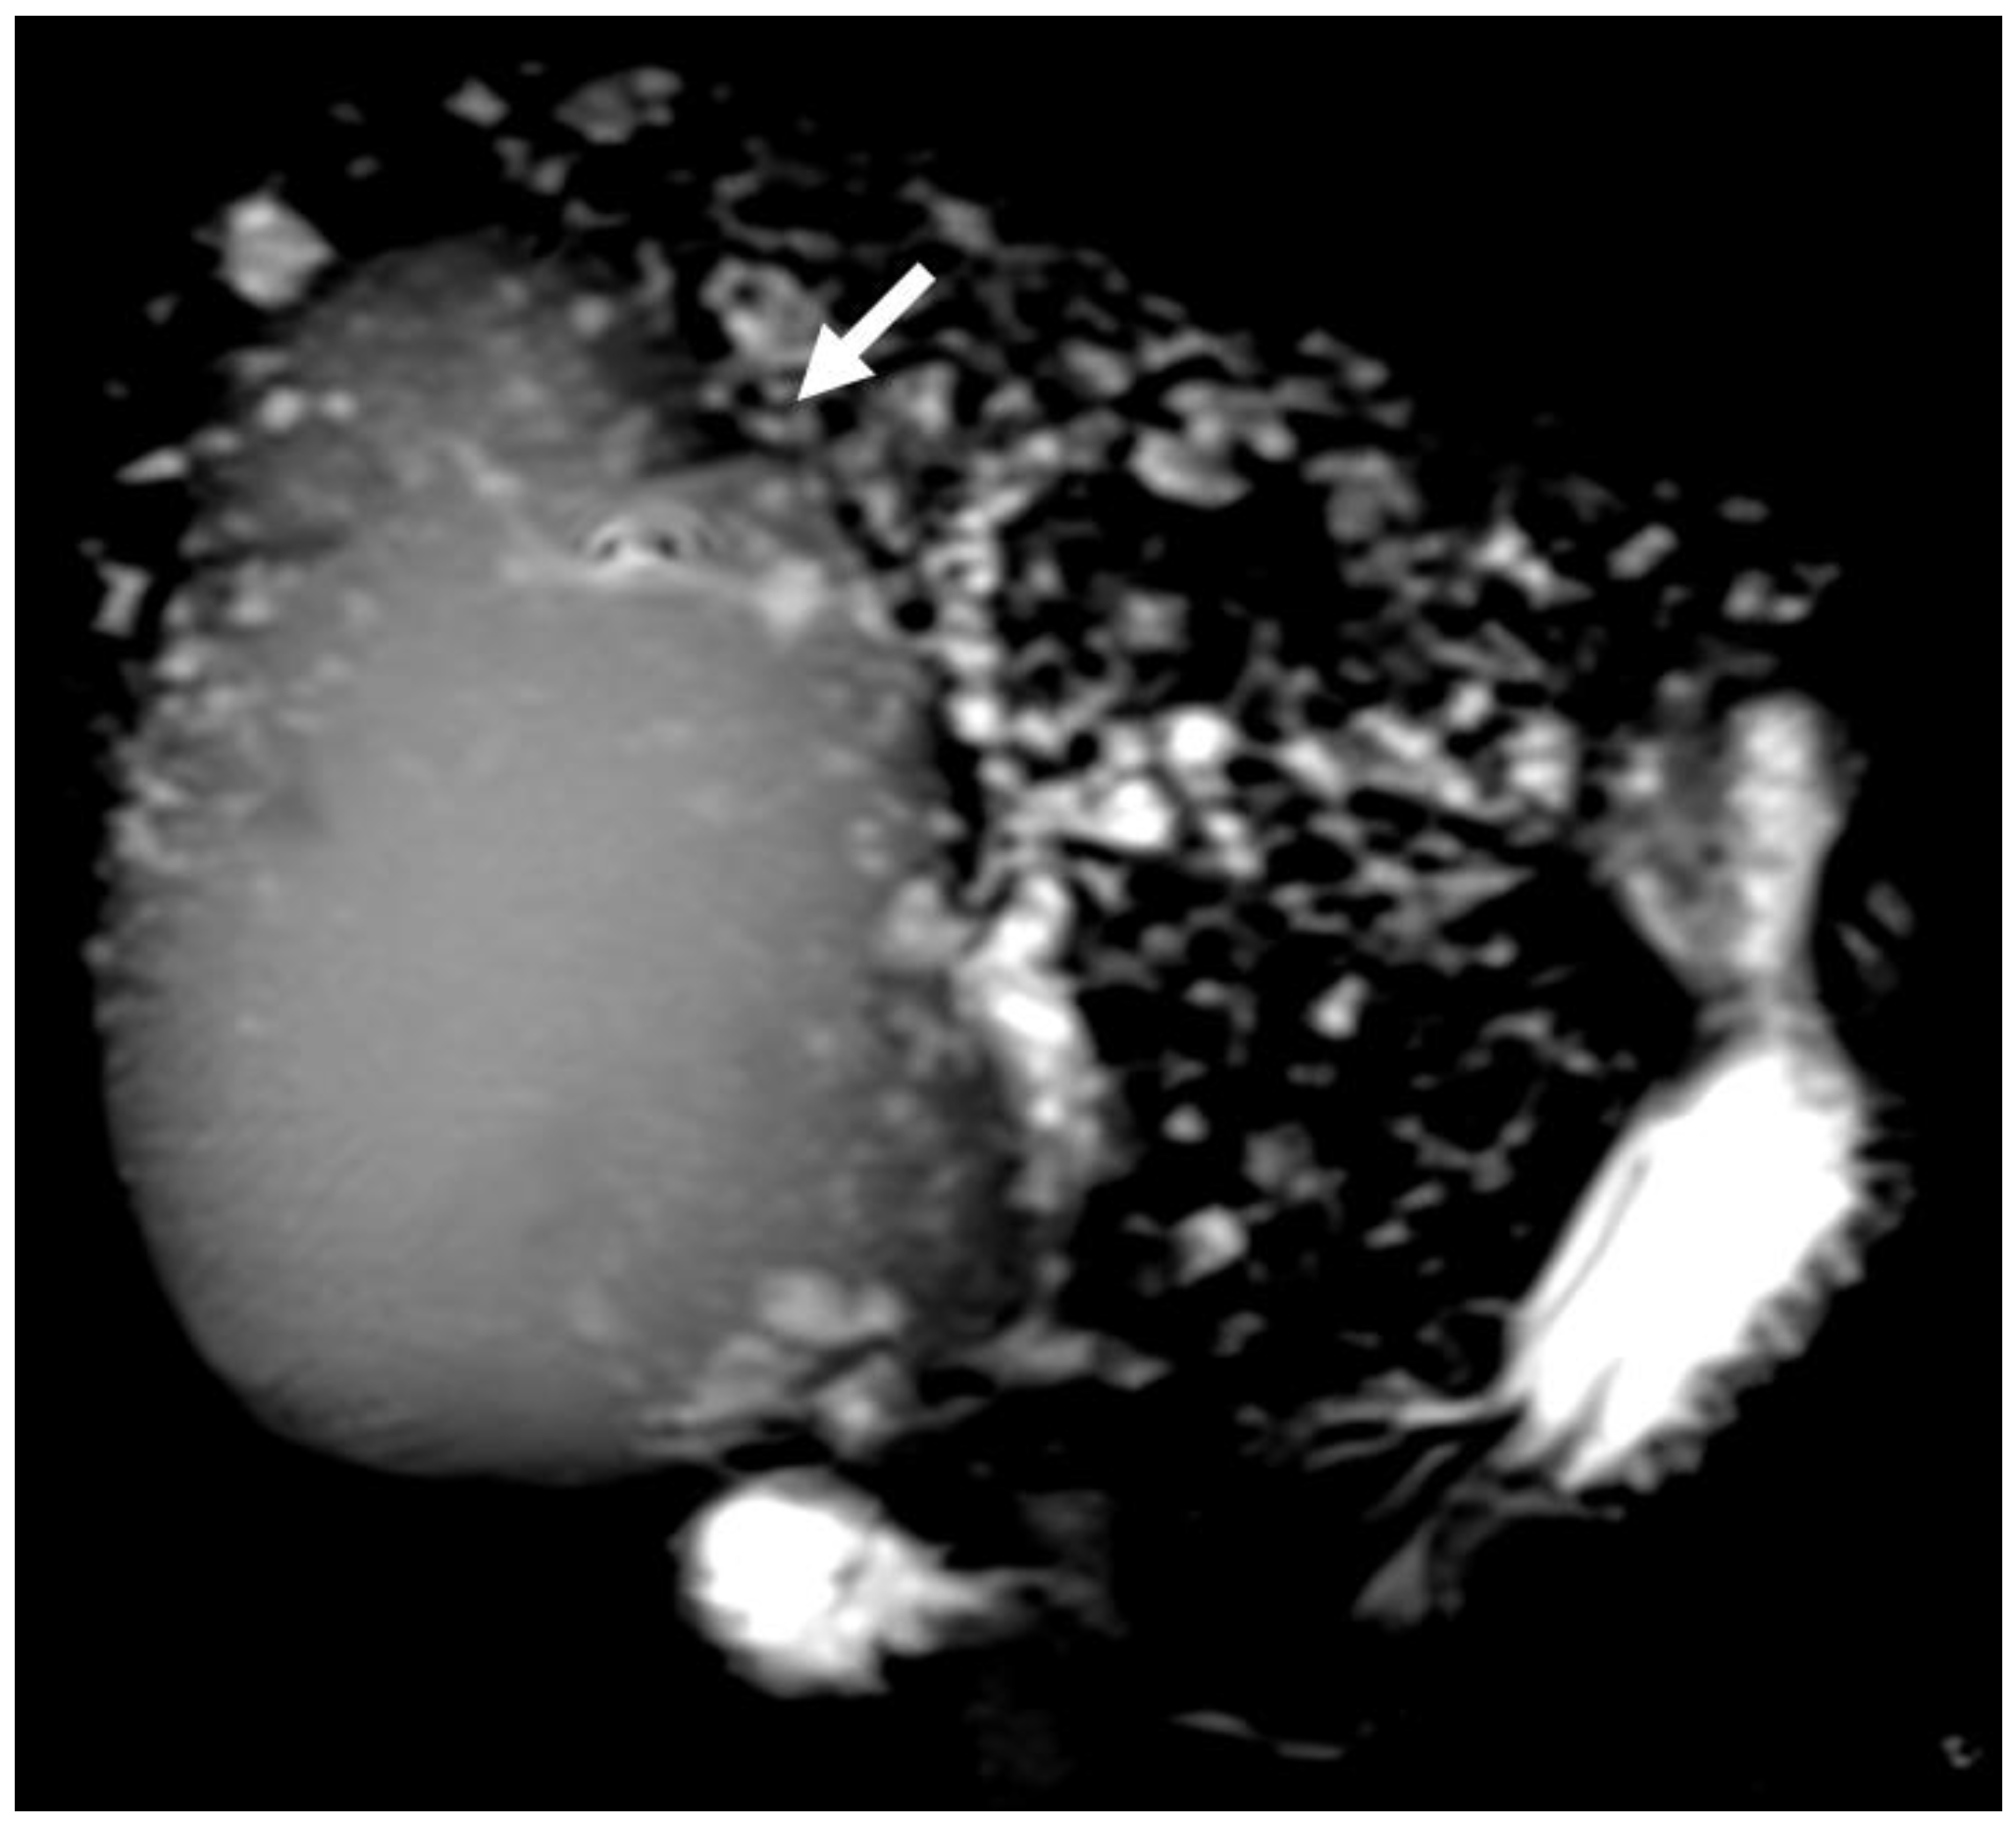

6.4. Hepatobiliary Mucinous Cystic Neoplasm

6.5. Diagnostic Management